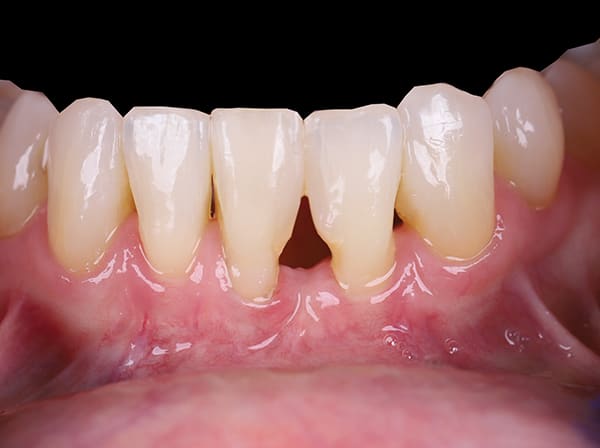

Black triangles in cervical embrasure areas are unesthetic and often cause patients to have difficulty with phonetics and hygiene. A 66-year-old woman presented to the periodontal office of Dr. Jason Stoner with excessive bleeding in the mandibular anterior region. She had a history of trauma to teeth Nos. 24 and 25 years prior, which were endodontically treated at the time of injury. Dr. Stoner's evaluation revealed a large resorptive defect on the distal extent of tooth No. 24. After considering different treatment options, the patient opted for removal of No. 24 and orthodontic therapy to achieve space closure post-extraction. Prior to removal of the tooth, Drs. James Hutta and Jeff Price were added to the treatment team to assist with orthodontics. Dr. Stoner extracted tooth No. 24 without complication, and the orthodontic phase took approximately 18 months. Upon completion of orthodontics a large residual black triangle remained between teeth Nos. 23 and 25. At this time, the patient's previous restorative dentist placed composite bonding, which the patient was not happy with. She then was referred to the author's office for evaluation of the residual Miller Class III defect. Exploiting the many benefits of bioactive Giomer Technology (Shofu, shofu.com), the author developed a treatment plan that would utilize both pink Giomer and white composite to satisfy the treatment objectives.